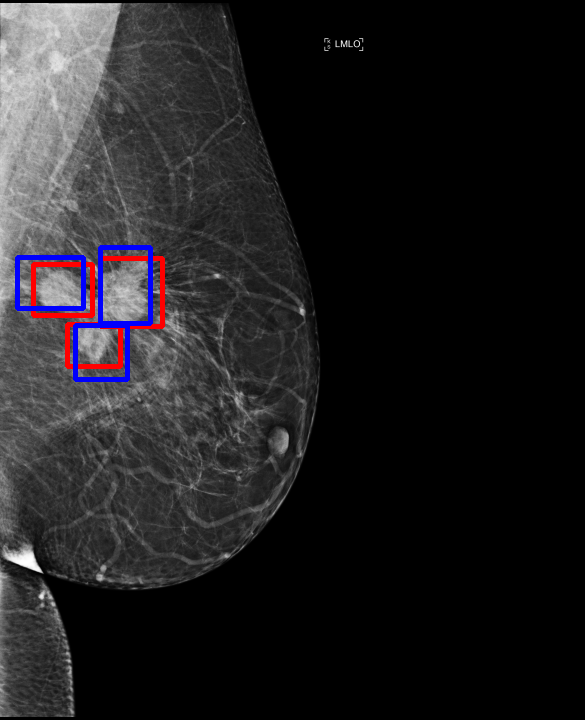

UDA has been extensively studied in case of natural images, utilizing techniques such as adversarial learning [21],pseudo-label training [6, 21, 40], image-to-image translation [40], graph reasoning [20], and adaptive mean Teacher training [6], improving domain adaptation efficiency of object detectors. Recently multiple works focused on using Mask autoencoders (MAE) methods in large-scale pretraining for vision models, involving masking parts of input and reconstructing them [12, 33]. However, these approaches overlook domain shifts. Alternatively, widespread utilization of Teacher-Student models, wherein a Teacher provides pseudo-labels for target domain (unlabeled images) to supervise a Student model, leads to notable adaptation improvements [40, 43]. However, these techniques face the challenge of incorrect predictions and excessive false positives per image due to low-quality pseudo-labels, particularly for medical imaging problems. Pseudo-labels are filtered from the Teacher model’s outputs based on the confidence score threshold. Selecting numerous pseudo-labels with low thresholds leads to inclusion of incorrect predictions, and compromising performance. Conversely, higher thresholds yield a limited number of pseudo-boxes, resulting in sub-optimal supervision. Existing Teacher-Student models often produce pseudo-labels riddled with errors and false positives, as illustrated in Fig. 1(a) and Fig. 1(b). Though [21, 40, 43] utilize techniques like adversarial alignment, weak-strong augmentation, and selective retraining of Student model to minimize the false positives in pseudo-labels, these approaches fail on medical images.

Contributions of this work. We note that screening mammography inherently differs from natural images, with breast abnormalities such as masses, asymmetries, and micro-calcifications, typically much smaller in comparison to the salient objects present in natural images, emphasizing the need for approaches specific to this problem. To address these issues, we make following contributions in this work: (1) We introduce D-MASTER, a transformer-based Domain-invariant Mask Annealed Student Teacher Autoencoder Framework for cross-domain breast cancer detection from mammograms (BCDM), integrating a novel mask-annealing technique and adaptive confidence refinement module. Unlike pretraining with mask autoencoders (MAEs) [12], leveraging massive datasets for training and then fine-tuning on smaller datasets, we present a novel learnable masking technique for the MAE branch that generates masks of different complexities, which are reconstructed by the DefDETR [44] encoder and decoder. Our approach, as a self-supervised task on target images, enables the encoder to acquire domain-invariant features and learn better target representations as shown in Fig. 1(c). (2) In Teacher-Student model, since the pseudo-label noise generated by the Teacher affects the Student model severely, we propose an adaptive confidence refinement module that progressively restricts the confidence metric for pseudo-label filtering. During the initial adaptation phase, soft confidence is applied allowing more pseudo-labels to learn better target representations. Subsequently, as confidence gradually increases, the focus shifts towards enhancing detection accuracy by prioritizing more reliable pseudo-labels. (3) We release a bounding box annotated subset of 1000 mammograms from the RSNA Breast Screening Dataset (referred to as RSNA-BSD1K) to support further research in BCDM. (4) We setup a new state-of-the-art (SOTA) in detection accuracy for UDA settings. We report a sensitivity of 0.74 on INBreast [25] and 0.51 on DDSM [18] at 0.3 FPI, compared to 0.61 and 0.44 using current SOTA respectively. Significant performance gains are also observed on our in-house and RSNA-BSD1K datasets.